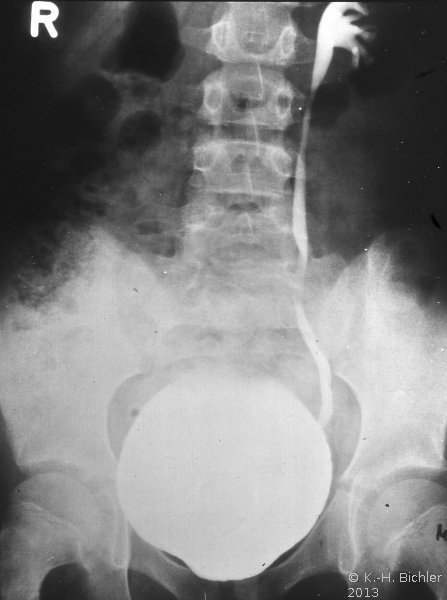

Neben der Anamnese, körperlicher Untersuchung, Messung des Blutdruckes sowie der Laboruntersuchungen: Urinstatus, Serumkreatinin und -Elektroylte ist die Sonographie zur Feststellung einer einseitig kleinen Niere zielführend (Abbildung 10a). Zur Diagnostik zählt fernerhin die NFZG (Abbildung 10b) bzw. Computertomographie.

Die Abbildungen zeigen die Anwendung von Sonographie und Miktionszysturethrogramm bei einer kleinen stummen Niere (Abbildung 13, 14).